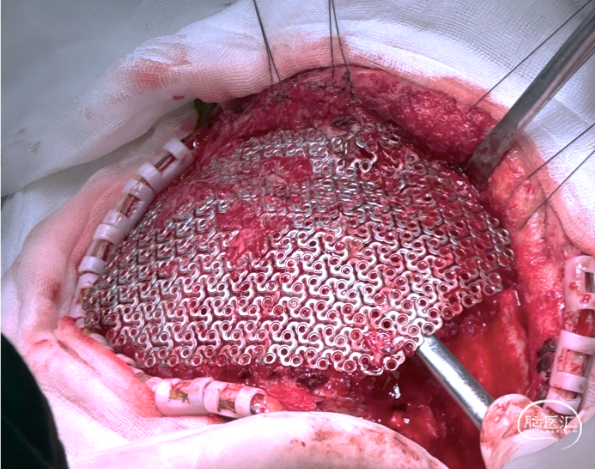

手术过程

可见角突处钛网凹陷,皮瓣状况良好。